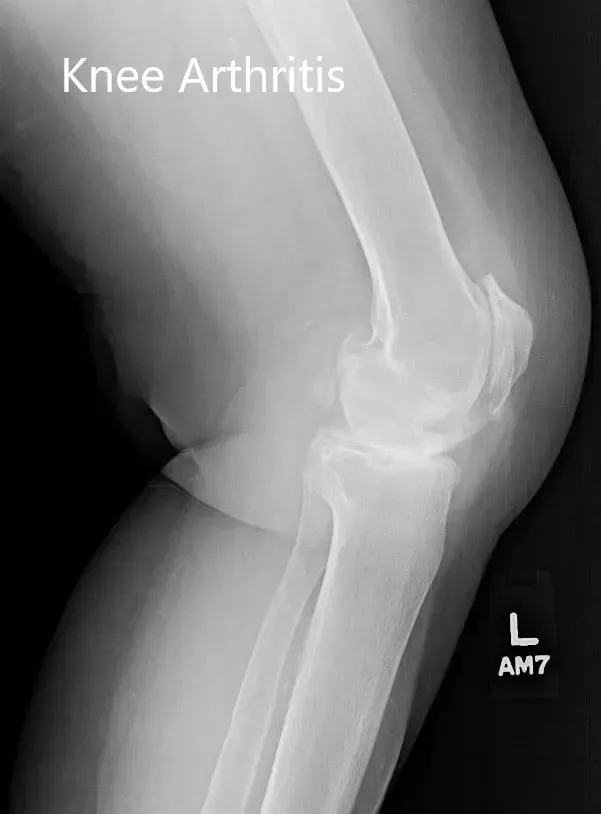

Los estudios de imagen revelaron osteoartritis bilateral severa. La rodilla izquierda estaba peor que la derecha. Teniendo en cuenta el dolor de rodilla limitante en el estilo de vida del paciente, se le recomendó un reemplazo total de rodilla izquierdo. Los riesgos, beneficios y alternativas se discutieron extensamente con el paciente y su hijo. Decidió seguir adelante con el procedimiento.

Radiografía preoperatoria de la rodilla izquierda que mostró osteoartritis severa en las vistas anteroposterior y lateral.